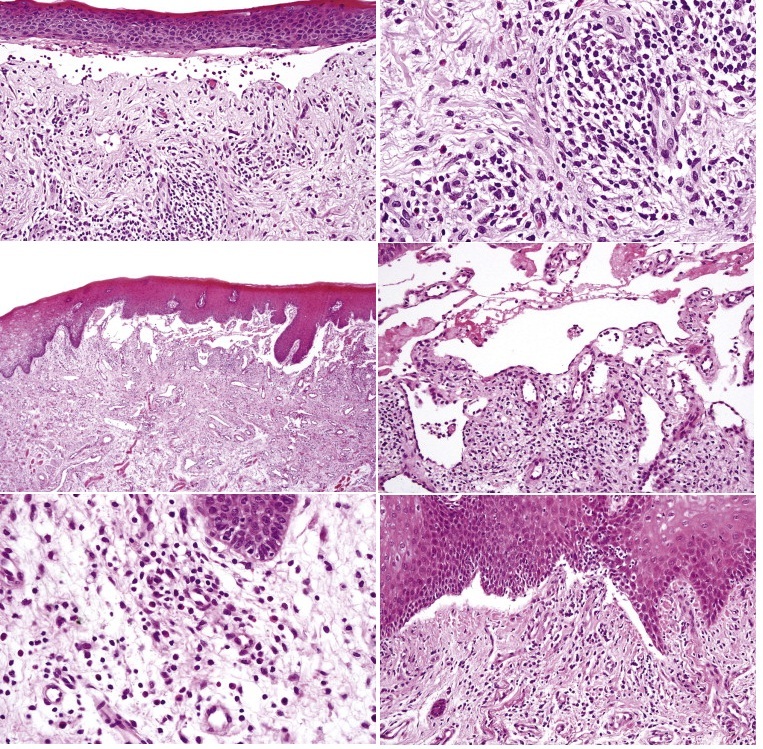

Cicatricial pemphigoid is an autoimmune blistering disease that presents with ulcers, blisters and erosions of mucosal surfaces, especially the eyes and mouth. The cleft in cicatricial pemphigoid is found in the basement membrane zone/subepidermal as the antigens are usually BPAg2,laminin 5 and alpha-6-beta-4 integrin. Direct immunoflourescence is identical to that of bullous pemphigoid showing linear IgG and complement deposits in the basement membrane zone.

Fig 2 Mucosal pemphigoid. There is a subepidermal blister containing eosinophils and lymphocytes.

Fig 3 Mucosal pemphigoid. Note the perivascular and interstitial infiltrate of lymphocytes, histiocytes, and conspicuous eosinophils.

Fig 4 Mucosal pemphigoid. Low-power view of oral lesion.

Fig 5 Mucosal pemphigoid. High-power view of blister cavity shown in Figure 4.

Fig 6 Mucosal pemphigoid. There is perivascular and interstitial lymphohistiocytic infiltrate with occasional plasma cells.

Fig 7 Mucosal pemphigoid. Biopsy specimen of an early oral lesion showing a cell-free subepidermal cleft.